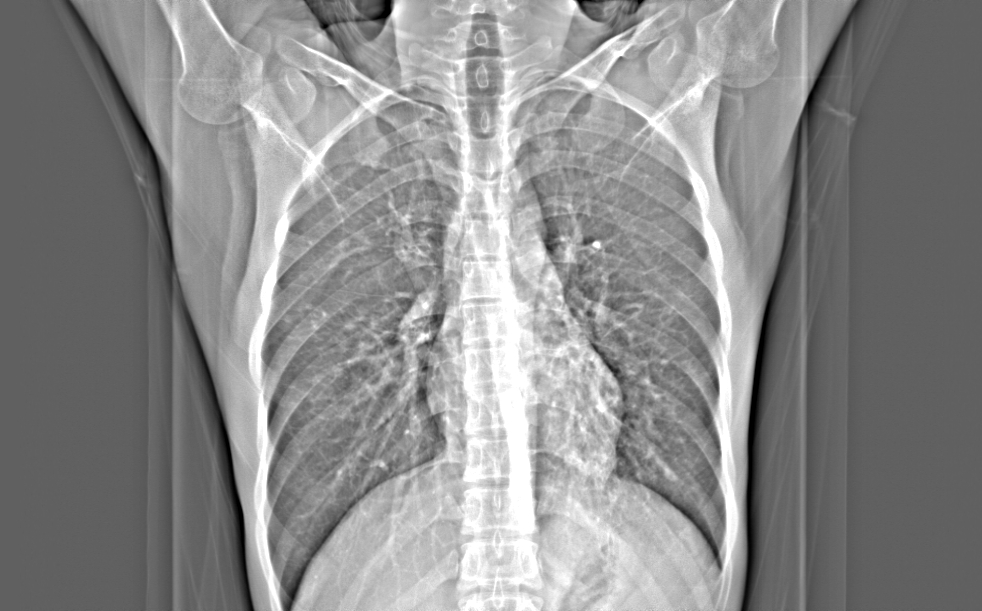

CT50204:男,29岁,咳痰,带血

男,29岁,咳痰,带血。双肺多发结节。

两肺均可见多发斑片状索条状及结节状密度增高影,密度不均,左肺尤著,部分且见透光区,考虑两肺继发性结核伴空洞形成。

两肺继发性肺结核(左肺部分病灶内空洞形成)。